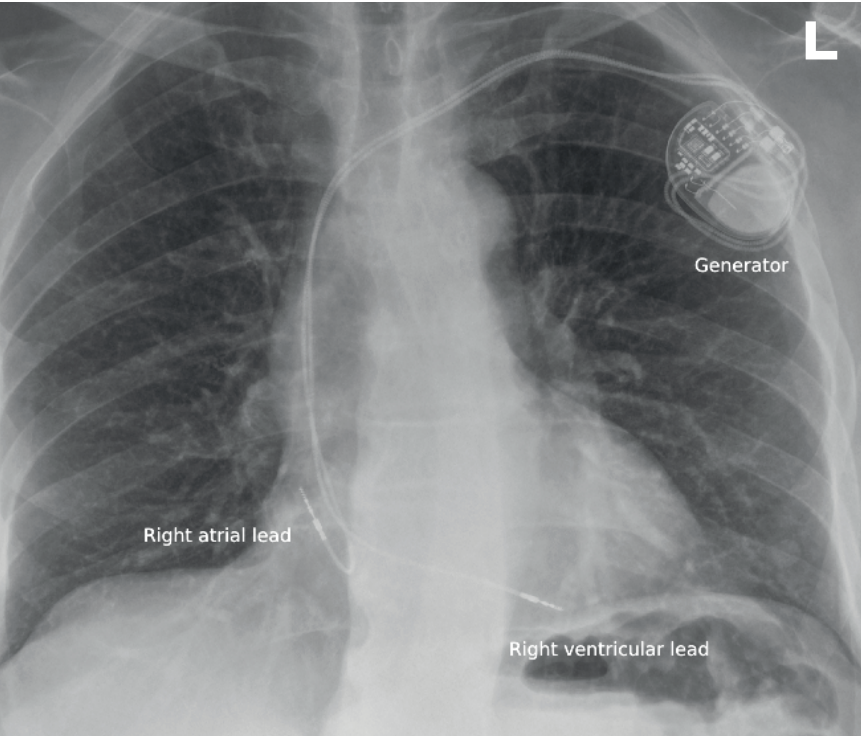

Most pacemakers are transvenous systems comprising a titanium pulse generator implanted in a subcutaneous chest wall pocket and connected to the myocardium via insulated leads introduced through the venous system (Figure 1).

Leads are typically secured to the endocardium using active screw fixation. Devices are usually implanted on the left side due to more straightforward venous access and avoidance of the dominant arm, although right-sided placement may be required in patients with venous access issues or prior infection.

Pacemaker systems are traditionally classified according to lead number and location. Dual-chamber devices with right atrial and right ventricular leads account for approximately two-thirds of implants, while the remainder are predominantly single-chamber ventricular systems.7